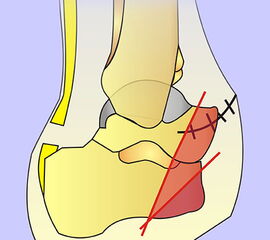

Schema der Amputationslinien im Bereich des Mittelfußes von der Seite.

Abbildung 41

Auf dem Niveau der Tarso-metatarsal-Gelenke (TMTG) kommen die operationstechnischen Prinzipien der TMA analog zur Anwendung (Abb. 41). Nach Absetzen in der Gelenkreihe werden die Knochenkanten nach medial, plantar und lateral abgeschrägt. Wesentlich ist, dass bei einer Amputation in der Lisfranc-Gelenklinie die Sehnenansätze des M. fibularis (peroneus) brevis immer und die Sehne des M. tibialis anterior häufig entfernt. Um eine Spitzfußstellung bzw. störende Seitdeviation zu umgehen, sollte nach Möglichkeit eine Resinsertion vorgenommen werden. Alternativen sind eine Durchtrennung der Achilles- und Tibialis-posterior-Sehne mit einer Sehnentransposition.

Problematik des nicht antagonisierten Sehnenzugs nach Lisfrancamputation. Die  Fußhebung ist ausgefallen. Durch Zug des M. trizeps surae resultiert eine Spitzfußstellung, die bei Neuropathie ein chronisches Ulkus im Bereich der Hauptbelastungszone hervorr

Abbildung 42